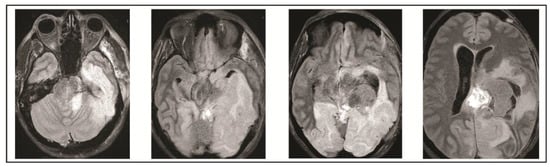

2. Case Presentation